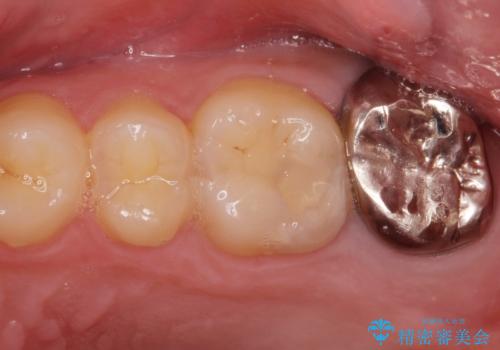

- 銀歯を良いものに変えたいとの事で来院。

過去に根の治療もされている歯だが土台が粗造なため根の治療からやり直しを行いゴールドクラウンにて治療を行いました。

また手前のはに虫歯があったためセラミックの詰め物で治療しました。